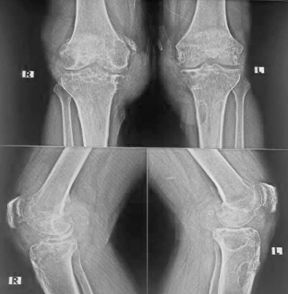

Figure 1. Pre op X-ray.

Tophi represent chronic urate deposition and are typically a late manifestation of gout. Subcutaneous tophi may occur even before the first gouty arthritis episode [2]. Radiologically, gout often presents with “punched-out” erosions without periarticular osteopenia [3].

A 63-year-old male presented with bilateral knee pain persisting for six years. The pain was described as dull, intermittent, and aggravated by walking or bending. There were no relieving factors. Physical examination revealed a fixed flexion deformity of 45° bilaterally, with further flexion possible only up to 90°.